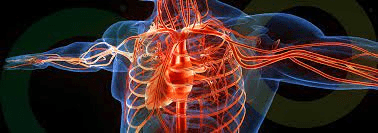

Paciente con arteriosclerosis en la vena carótida derecha provocándole convulsiones al momento de ponerse de pie, ¿qué especialista le recomendaría?

Angiólogo/Cardiólogo